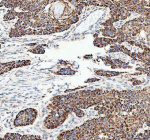

IHC analysis of CAMKK2 using anti-CAMKK2 antibody. CAMKK2 was detected in a paraffin-embedded section of human esophageal squamous carcinoma tissue. Heat mediated antigen retrieval was performed in EDTA buffer (pH 8.0, epitope retrieval solution). The tissue section was blocked with 10% goat serum. The tissue section was then incubated with 2 ug/ml rabbit anti-CAMKK2 antibody overnight at 4oC. Peroxidase Conjugated Goat Anti-rabbit IgG was used as secondary antibody and incubated for 30 minutes at 37oC. The tissue section was developed using an HRP secondary and DAB substrate.